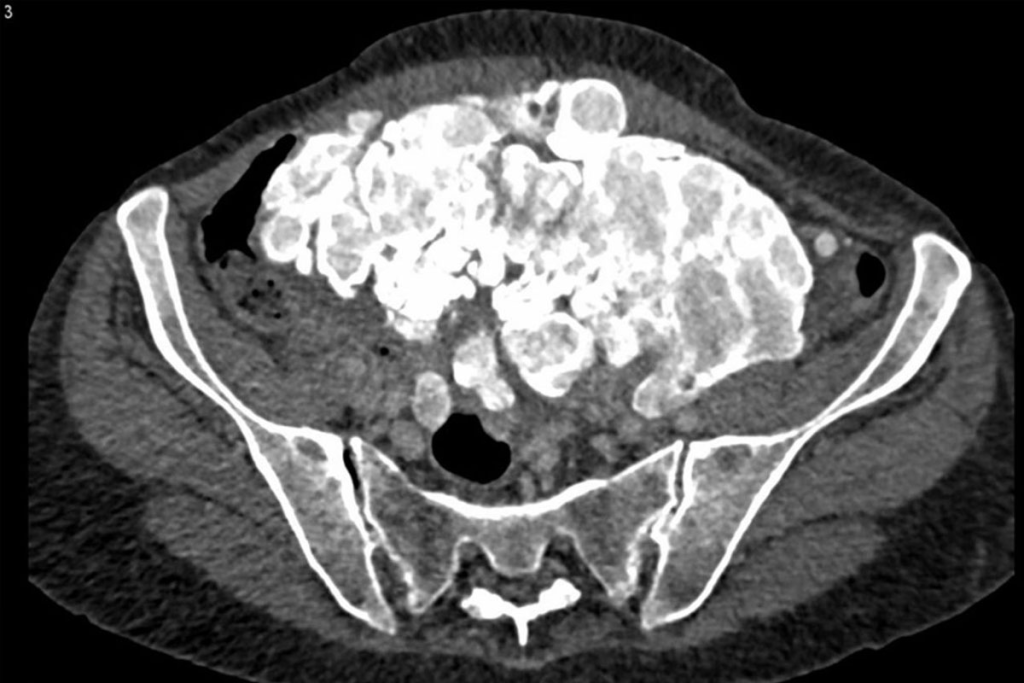

Common Sites of Metastasis Detected by CT

CT scans are key in finding cancer spread in organs like the liver, lungs, and bones. They help doctors know how far cancer has spread and plan treatment. This is very important for cancer care.

Lymph Node Metastases Assessment

Lymph node metastases are key in cancer staging. They show cancer has spread. CT scans can check lymph nodes by looking at their size and shape. Big lymph nodes might mean cancer has spread.

Contrast-enhanced CT is better for looking at lymph nodes. It helps tell them apart from blood vessels. Checking lymph nodes on CT scans is important for knowing how far cancer has spread and for treatment planning.